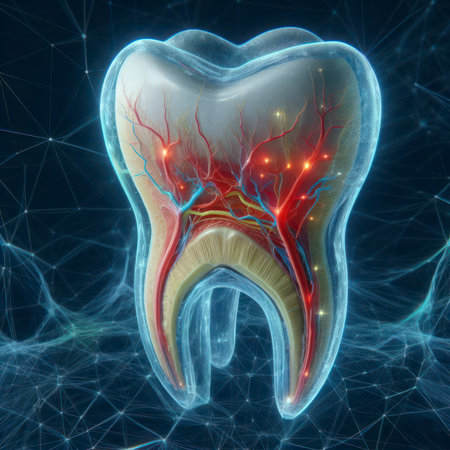

Delicate structures within a tooth illustrate dental complexity and biological function.

A 3D model of a human molar tooth with visible internal structure on blue background

Tooth model displaying its complex internal structure including enamel, dentin, pulp, and root canals, standing against a vibrant background of colorful, out of focus lights

Anatomical intricacy: tooth structure, nerve, with a visible cartilaginous stage, detailed layers and components of a tooth, emphasizing the complex interplay of dental anatomy

This image depicts a detailed anatomical model of a human tooth, showcasing the intricate internal structures, including nerves and blood vessels, essential for educational and healthcare purposes.

Transparent tooth model displaying detailed internal anatomy, including nerves, blood vessels, and pulp structure, isolated on a gray background.

High-Resolution 3D Tooth Model with Nerves, Roots, and Holographic Interface

AI generated 3D rendering of a translucent human tooth revealing an intricate glowing neural and vascular network in orange over a deep blue background conveying futuristic biovisual data processing

An intricate view of a tooth nerve root structure, showcasing dental anatomy and emphasizing the need for preventive oral care.

Detailed cross-section of a human tooth displaying enamel, dentin, pulp, and root anatomy. Educational medical illustration on a gradient blue background.

An AI generated illustration of a white tooth with internal structure exposed and visible

An intricate view of a tooth nerve root structure, showcasing dental anatomy and emphasizing the need for preventive oral care.